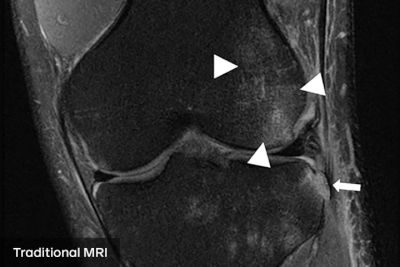

fastMRI团队多年来一直在研究这个问题,但周二他们在《 American Journal of Roentgenology》杂志上发表了一项临床研究,他们说这证明了他们的方法的可信度。该研究要求放射科医生根据传统的核磁共振扫描和人工智能增强的患者膝盖扫描进行诊断。研究报告称,当面对传统扫描和AI扫描时,医生做出的评估完全相同。